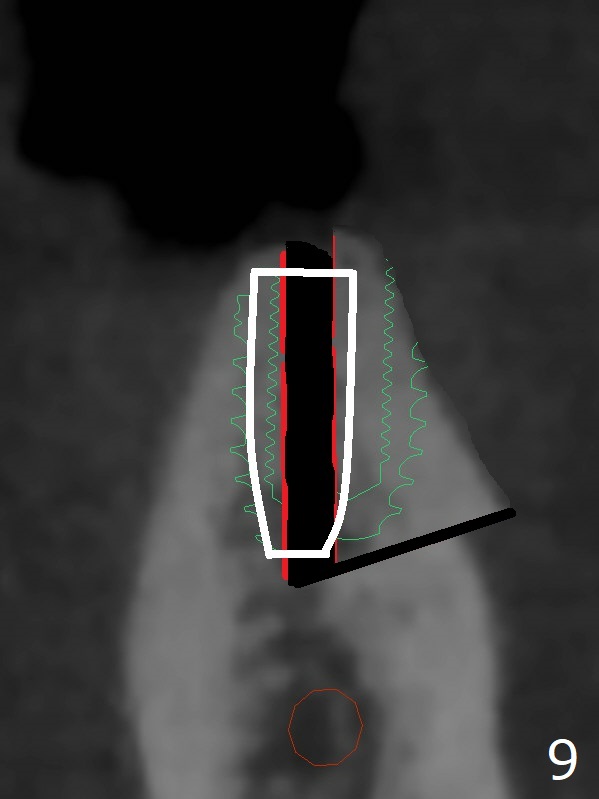

When implants at #4, 13 and 14 are placed, the patient wonders how many more implants are needed. From 0 (considering a lower RPD) to 5 (#3, 19, 20, 25 and 30). The tooth #3 seems to have periodontal-endodontic disease (Fig.1,2). Since the ridge is narrow at #19 and 20 (Fig.3), ridge split at #19 and a 1-piece implant at #20 are planned (Fig.4,5-9). The implant at #19 will be placed in an ideal prosthetic position (Fig.5). The ridge transverse bony cut will be made free hand in the middle (Fig.6,6'), followed by 2 vertical cuts and 1 apical transverse one in the 1st stage of procedure. In order to rotate the buccal block easier (Fig.6 pink curved arrow), the apical transverse cut will be wedge in shape (Fig.6 (red), 6' (double lines), 7 (black)). In the 2nd stage, the ridge top split will be extended by using a chisel (Fig.7 longer red line) and the buccal block will be pushed buccally (Fig.8). A guide will be seated to finish osteotomy (Fig.9 white) and implant placement.